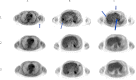

PET scans performed before treatment (row 1), at 6 months after treatment (row 2), and at 12 months after treatment (row 3). Column A (arrow) shows untreated axillary lesion that was no longer apparent at 6 and 12 months after treatment. Column B (arrow) shows one of two treated hepatic lesions, which showed complete response to treatment at 6 and 12 months after treatment. Column C (arrows) shows three of five untreated hepatic lesions, which also showed complete response to treatment at 6 and 12 months after treatment.